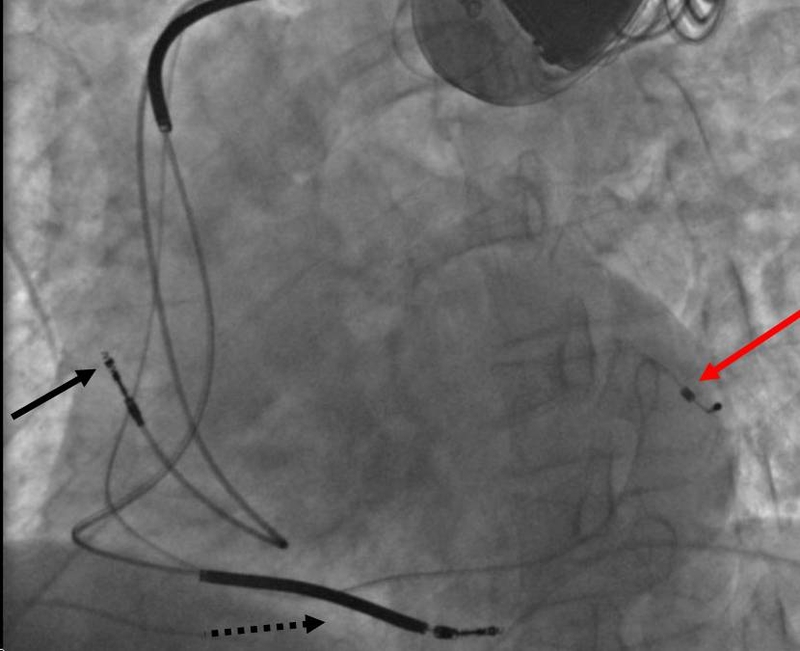

Phương pháp này sử dụng một thiết bị cấy ghép, gồm các điện cực đặt vào thành tim giúp đồng bộ hóa hoạt động của các buồng tim, đặc biệt là hai tâm thất. Khi tim bị suy giảm chức năng bơm máu và các buồng tim không còn hoạt động nhịp nhàng, khả năng cung cấp máu nuôi cơ thể sẽ giảm rõ rệt dẫn đến các triệu chứng như khó thở, mệt mỏi và đau ngực. CRT trong suy tim giúp cải thiện sự phối hợp co bóp của cơ tim, qua đó nâng cao hiệu quả bơm máu, làm giảm gánh nặng lên tim và làm giảm các triệu chứng lâm sàng.

Khi các buồng tim không co bóp nhịp nhàng, tim sẽ bơm máu kém hiệu quả làm xuất hiện các triệu chứng như khó thở, mệt mỏi hoặc phù. CRT sử dụng thiết bị cấy ghép gồm các điện cực kích thích đồng thời hai bên tâm thất nhằm khôi phục sự phối hợp trong hoạt động co bóp của tim. Nhờ đó, lưu lượng máu được cải thiện, làm giảm áp lực lên tim và giảm triệu chứng suy tim. Ngoài việc cải thiện chất lượng sống, liệu pháp này còn góp phần làm giảm tỷ lệ nhập viện và nguy cơ tử vong liên quan đến suy tim mạn tính.